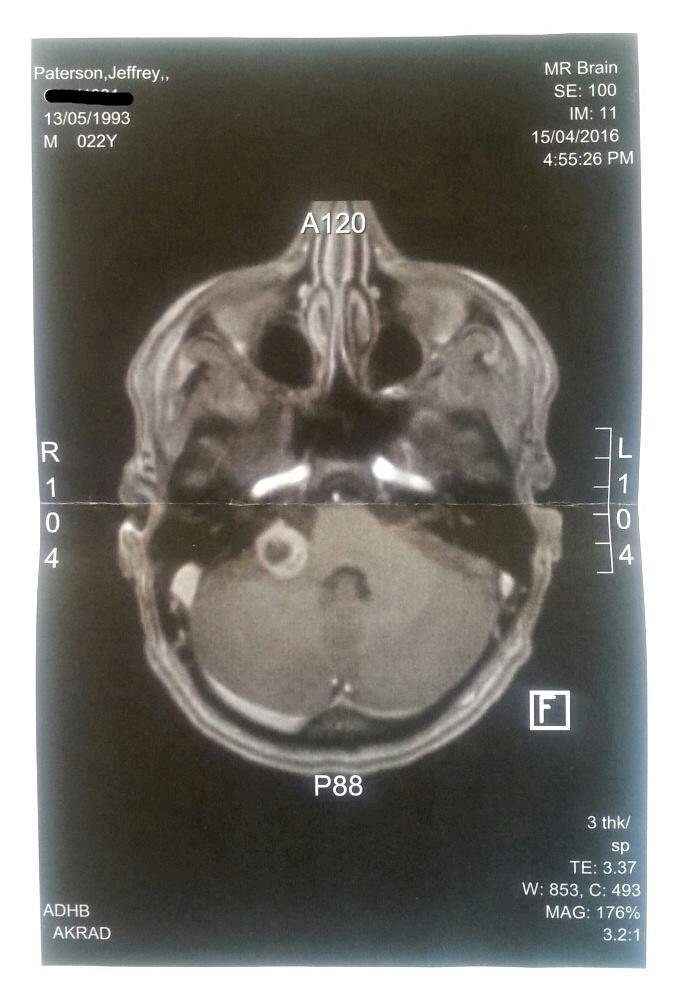

Main image

How big my brain tumour was back in mid April to how big it was yesterday. (Left mid April, right is Sunday).

I don't like them as much as they seem to like growing in me.